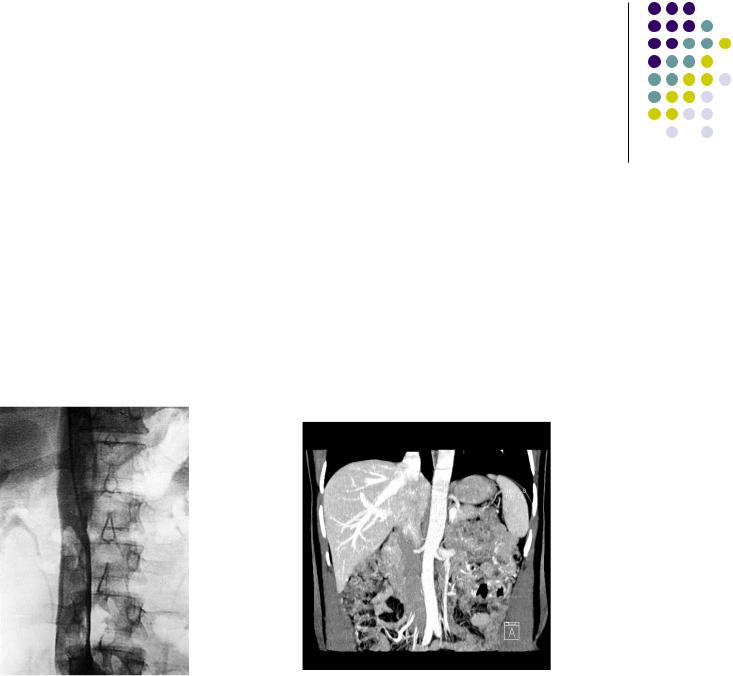

Рентгенологические методы исследования венозного русла

Ангиография (флебография) ретгеноконтрастный метод изучения венозного русла для определения характера и локализации патологического процесса(гипоили аплазия, рефлюкс, тромбоз,окклюзия). Сочетается с рентгенэндовазальными процедурами (фильтр, стент)

КТ-ангиография, сКТ-ангиография, МРТ-ангиография методы контрастного и безконтрастного исследования, применяемые для верификации сложных видов патологии вен